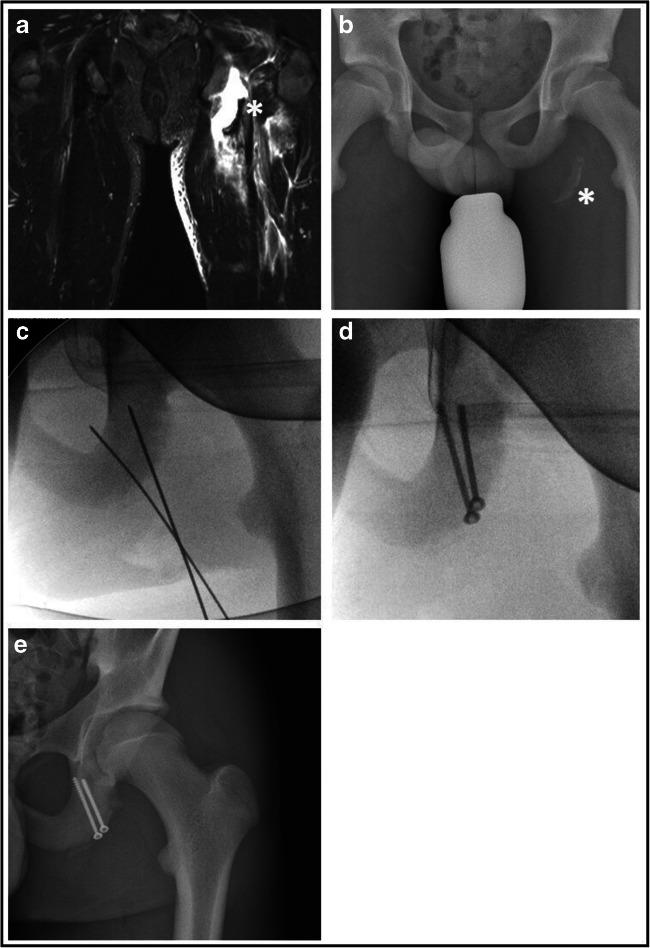

Eleven adolescents with an acute or chronic mean fragment dislocation of 3.3 cm (SD ± 1.7) underwent surgical intervention in the assigned period. The mean post-operative PHAT score was 86.9 (0-100, SD ± 11.9) and thus good to excellent. The majority of adolescents (10/11) was able to return to their pre-injury sports, whereas 63.6% achieved full or nearly full level.

Surgical refixation or restoration of aphoyseal avulsion fractures of the ischial tuberosity result in good to excellent outcomes and return to sport rates, irrespective of the type of intervention. Here prompt diagnosis with a timely intervention seems more promising than delayed interventions in chronic cases. Beyond 1.5 cm of fragment displacement affected patients should be counselled for surgical intervention.